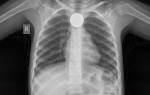

- рентген с контрастированием барием (для выявления рубцов, стриктур, стенозов, кардиоспазма);